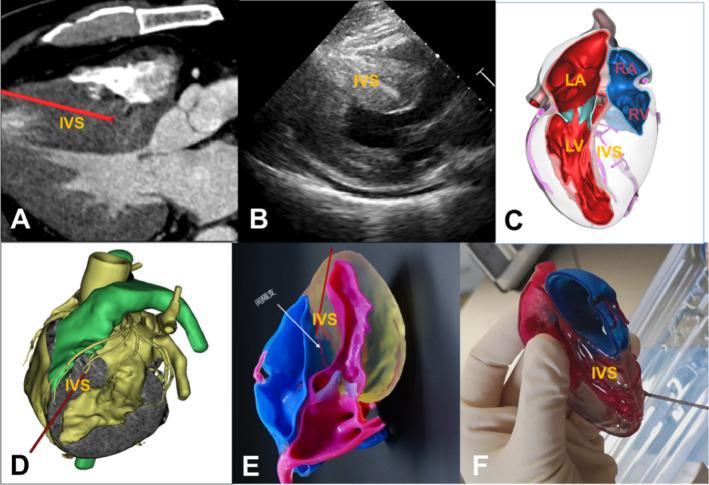

Heart diseases remain the top threat to human health, and the treatment of heart diseases changes with each passing day. Convincing evidence shows that three-dimensional (3D) printing allows for a more precise understanding of the complex anatomy associated with various heart diseases. In addition, 3D-printed models of cardiac diseases may serve as effective educational tools and for hands-on simulation of surgical interventions. We introduce examples of the clinical applications of different types of 3D printing based on specific cases and clinical application scenarios of 3D printing in treating heart diseases. We also discuss the limitations and clinically unmet needs of 3D printing in this context.